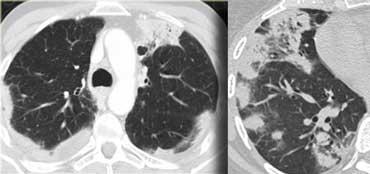

Bệnh nhân với Ung thư hạch bạch huyết lan tỏa.

Lưu ý phân bố khu trú của tổn thương.

Đặc điểm này có giá trị trong việc phân biệt Ung thư hạch bạch huyết lan tỏa với các nguyên nhân khác gây dày vách liên tiểu thùy như phù phổi hoặc sarcoidosis.

Ngoài ra còn có hình ảnh hạch to.

Hình ảnh

Bệnh nhân khác với Ung thư hạch bạch huyết lan tỏa có dày vách liên tiểu thùy (mũi tên vàng).

Kèm theo tràn dịch màng phổi (mũi tên xanh) và tổn thương di căn phổi (vòng tròn).